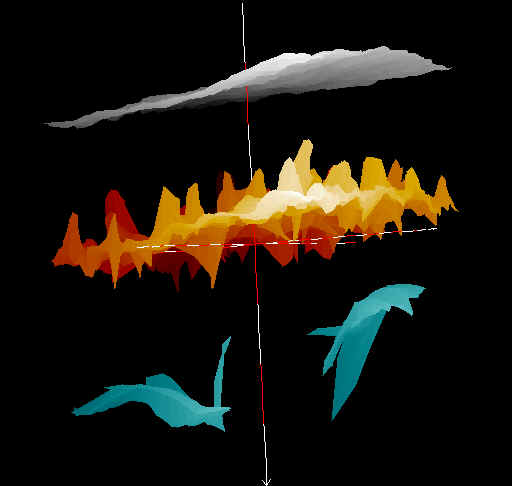

20 MHz 3D images

| Misc. |  Cellulite, arm |

Microdialysis tube |

Intradermal nevus |

Highlight. intrad. nevus |

| Misc. |  Ageband, forearm |

Nevus, skin parallel cut |

Normal, overlying hairs |